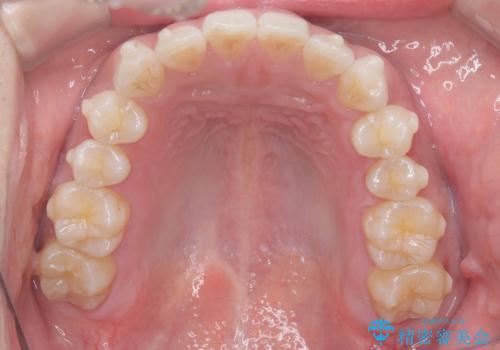

歯のデコボコを治したい|インビザラインで綺麗な歯並びに!|矯正期間は6ヵ月!

- 歯のデコボコが気になるを主訴に来院された患者様です。

インビザラインで歯は抜かずに非抜歯でデコボコを改善しました。

インビザラインで叢生の改善を行いました。

歯は抜かずに、拡大と少しのIPRで並べました。

矯正期間は半年です。

綺麗な歯並びを手に入れ大変ご満足していただきました。